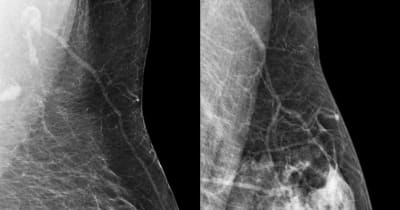

アジア人は多いとされる

高濃度乳房/デンスブレスト

マンモ検査をすると

「あなたの胸はデンスブレストなので

定期的な検診をお勧めします」

実際に私もマンモで「異常無し」

と言われた4ヶ月後には

自分で2cm程のシコリを

見つけたわけだから

高濃度乳腺の影に乳がんが

隠れていたと言う事だよね。。